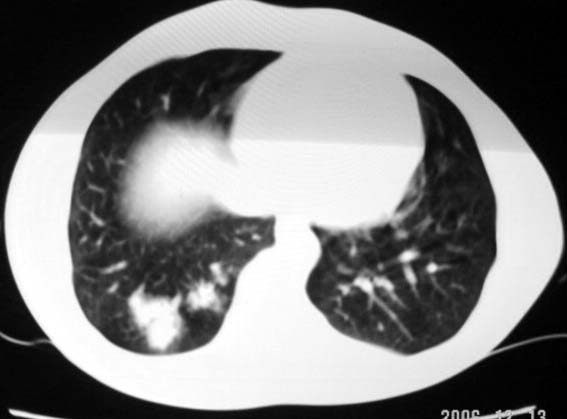

标题: CT5614:外伤病人男,20岁,右上腹痛.余肺野(-)

外伤病人男,20岁,右上腹痛,ct显示:右肺下叶后基地段见斑片状高密度影,密度不均,边界清,考虑1,右肺下叶肺挫伤;2,炎症。

其次,病灶较多并散布在右下肺底,纵肺比例明显小于50%,与膈肌以及后壁胸膜有轻度粘连。且其内密度不均匀,最大的那个结节影里面有较致密密度,胸椎旁似乎还有液平面。也就是说右下肺炎性改变可以肯定。

可以肯定的是与外伤无关。肺挫伤是片状渗出影:边缘比中心密度低,呈毛玻璃状,如果是结节状肺挫伤(肺内血肿)应该边缘光滑,不会与后壁胸膜有轻度粘连。此病灶分叶状,周围有卫星灶(纤维条索影及小结结影),考虑结核.